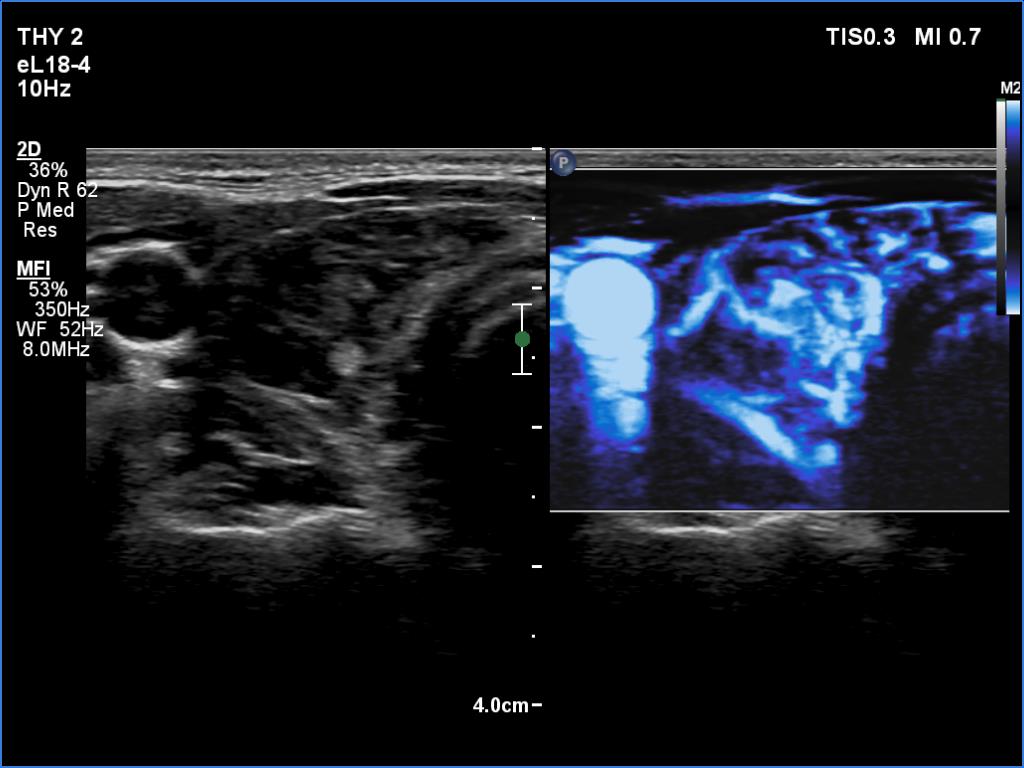

Ultrasonography. The thyroid was deeply hypoechoic and had numerous discrete iso/hyperechoic lesions. The latter had irregular shape and borders. The vascularity was increased. None of the discrete lesions corresponded to pathological nodules.